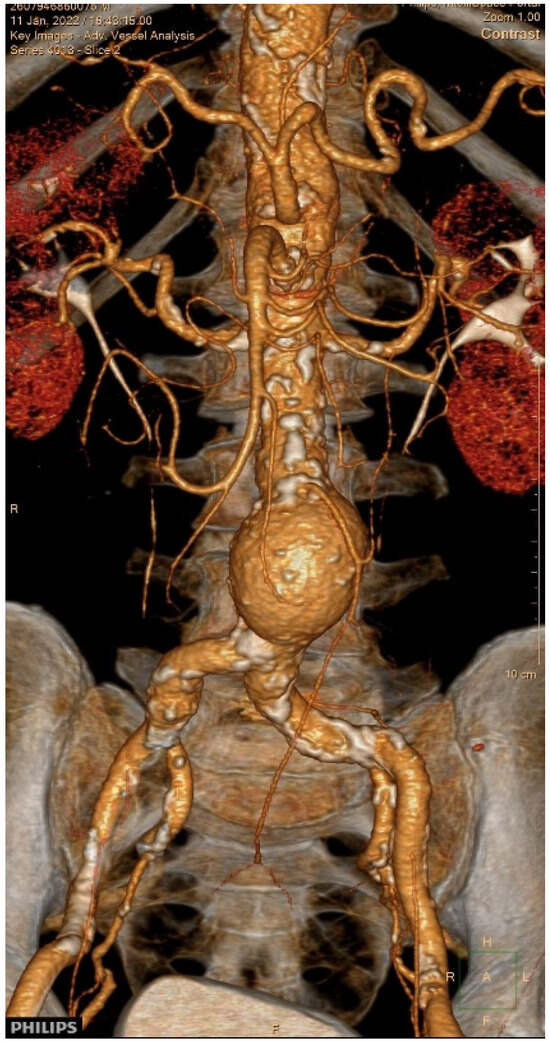

Simultaneous Transcatheter Aortic Valve Replacement and Endovascular Aortic Aneurysm Repair—The First Case in Serbia

Background and Clinical Significance: Concomitant severe aortic stenosis (AS) and abdominal aortic aneurysm (AAA) in elderly patients presents a significant therapeutic challenge. While transcatheter aortic valve replacement (TAVR) and endovascular aneurysm repair (EVAR) have become established minimally invasive treatments for high-risk patients, [...] Read more.

Background and Clinical Significance: Concomitant severe aortic stenosis (AS) and abdominal aortic aneurysm (AAA) in elderly patients presents a significant therapeutic challenge. While transcatheter aortic valve replacement (TAVR) and endovascular aneurysm repair (EVAR) have become established minimally invasive treatments for high-risk patients, simultaneous management of both conditions remains rare. Case Presentation: We report the first documented case in Serbia of a simultaneous TAVR and EVAR in a 75-year-old male with severe symptomatic AS and AAA. The patient had a history of hypertension, diabetes mellitus, atrial fibrillation, prior radiofrequency pulmonary vein ablation, and pacemaker implantation. Echocardiography demonstrated severe AS with a transvalvular gradient of 116/61 mmHg, an aortic valve area of 0.6 cm2, and a left ventricular ejection fraction of 30–35%. Coronary angiography revealed 50–60% stenosis of the right coronary artery. Following evaluation by a multidisciplinary Heart and Vascular Team, a combined procedure was performed under general anesthesia via bilateral femoral access. TAVR with a Medtronic Evolut R valve was successfully deployed, followed by EVAR with satisfactory stent graft positioning and angiographic results. The patient’s postoperative course was uneventful, and he was discharged on the ninth day. At six-month follow-up, echocardiography showed optimal valve function, and CT identified a type II endoleak, which was managed conservatively. Conclusions: This case demonstrates the feasibility and safety of simultaneous TAVR and EVAR in a high-risk elderly patient, emphasizing the importance of careful preoperative planning and a coordinated multidisciplinary approach. Further studies are warranted to establish standardized guidelines for the management of patients with coexisting severe AS and AAA. Full article

Show Figures

Figure 1